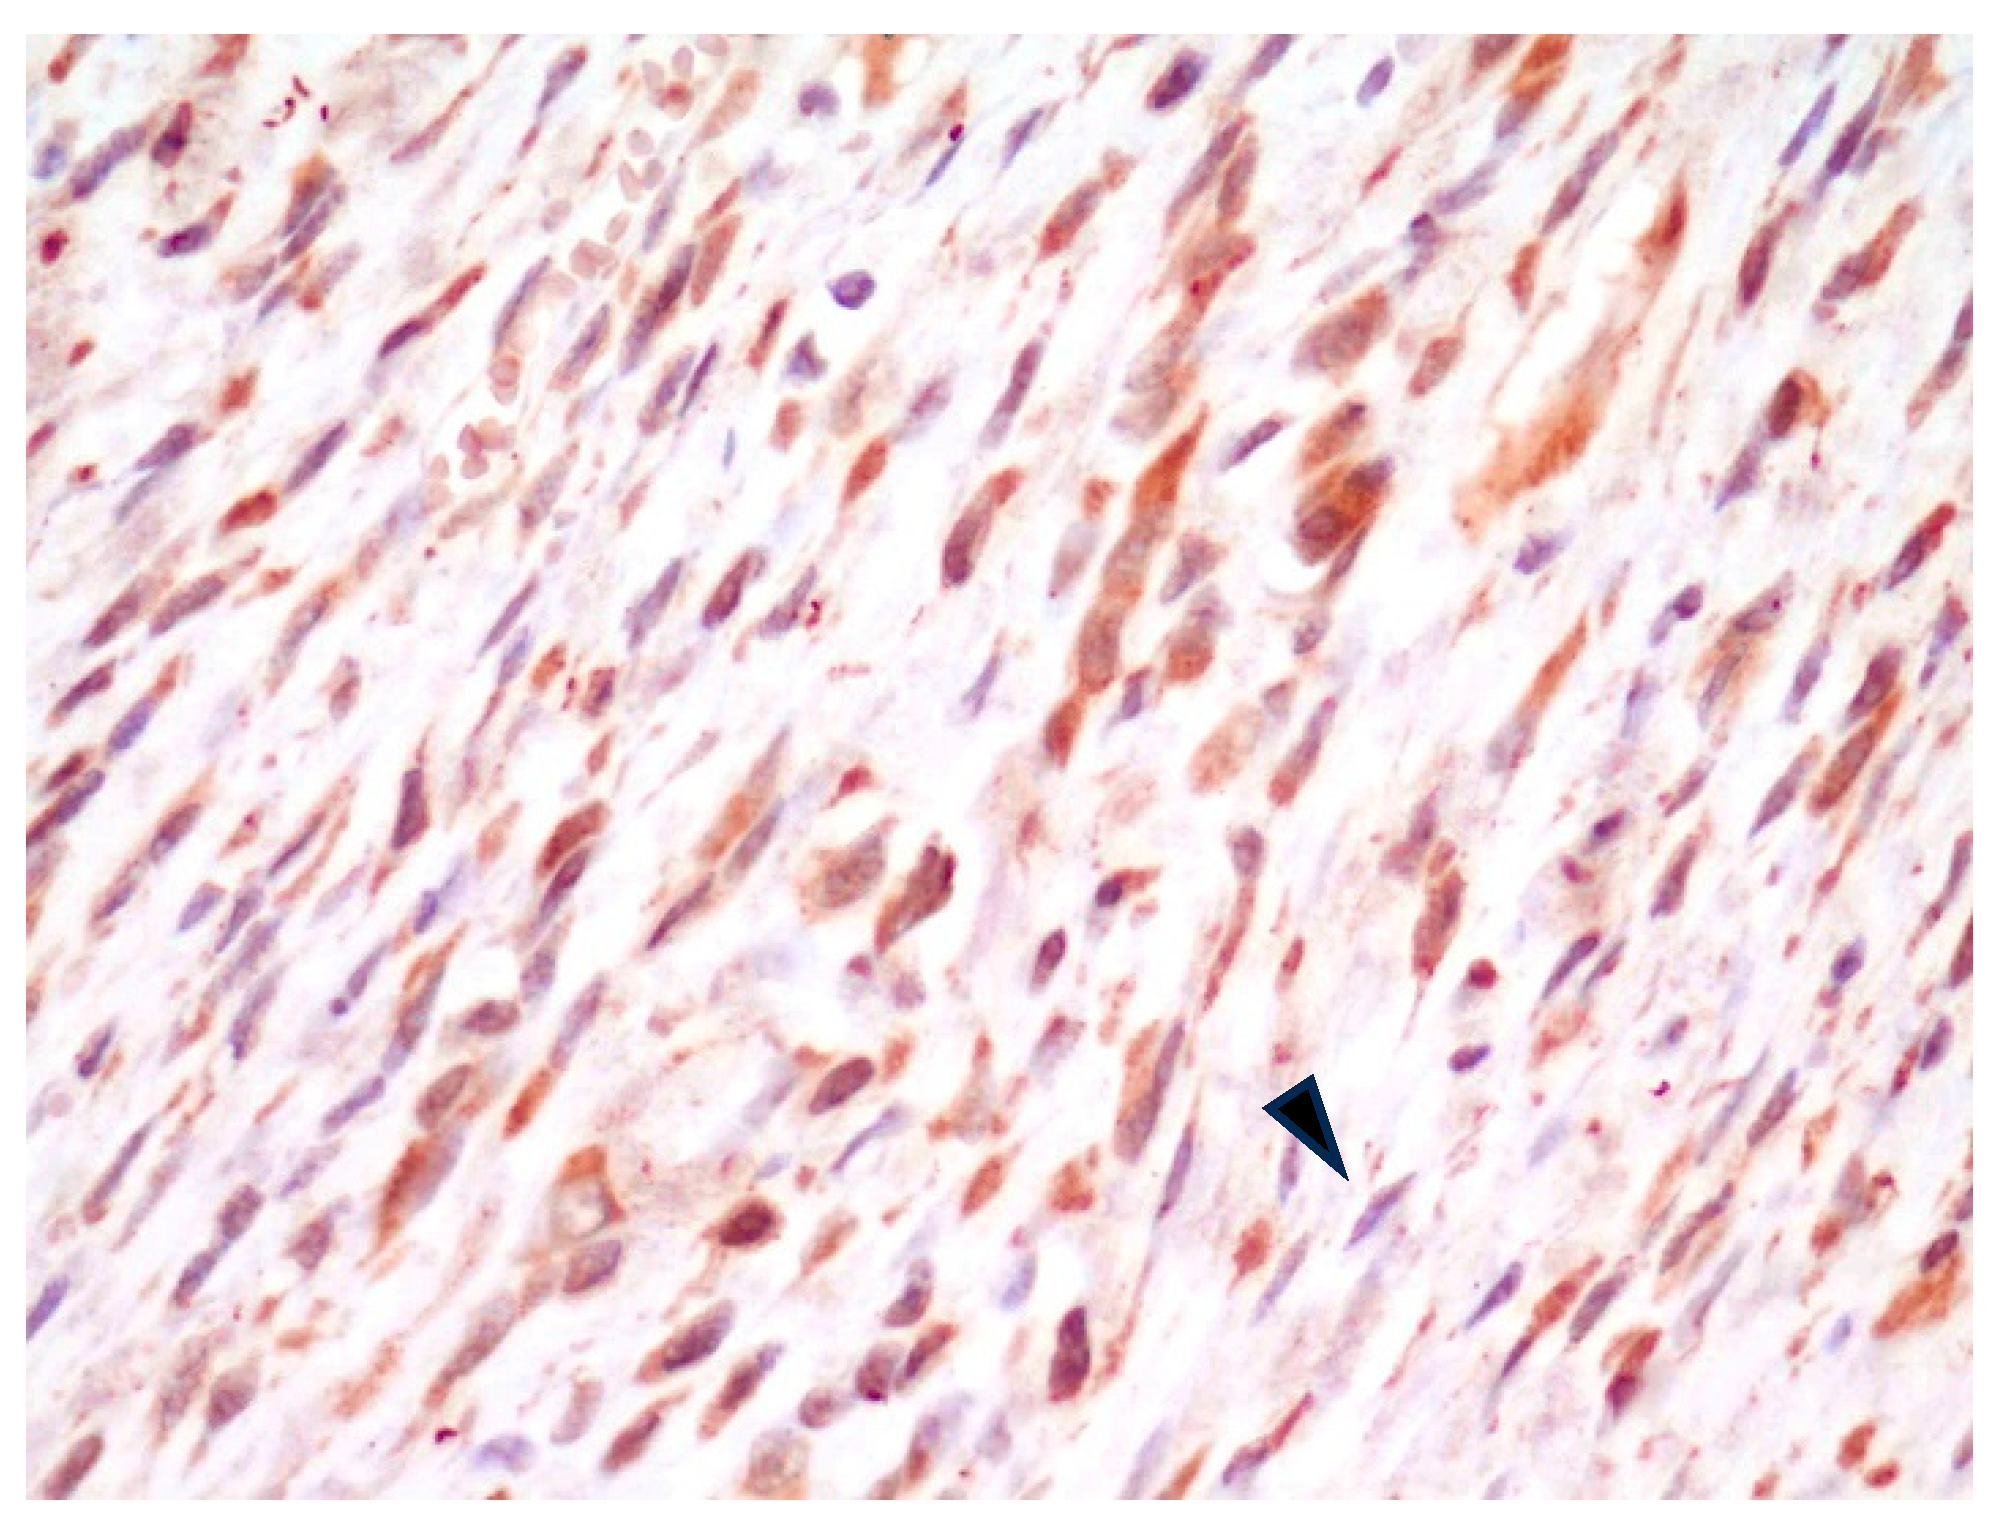

In all FISS cases, in the tissue composing the surgical margins, regardless of the histopathological interpretation of the margin status, spindle cells with plump nuclei and moderate cytoplasm (interpreted as fibroblasts) had consistent, moderate intracytoplasmic positive staining, while spindle cells with slender nuclei and thin scant cytoplasm (interpreted as fibrocytes) were either mildly positive or negative (Figure 3).

Figure 3.

FISS, margin of fibrosarcoma. Fibroblasts have diffuse, mild-to-moderate cytoplasmic positivity for αv integrin, whereas fibrocytes are mildly stained or negative (arrowhead). IHC for αv integrin, 400×.